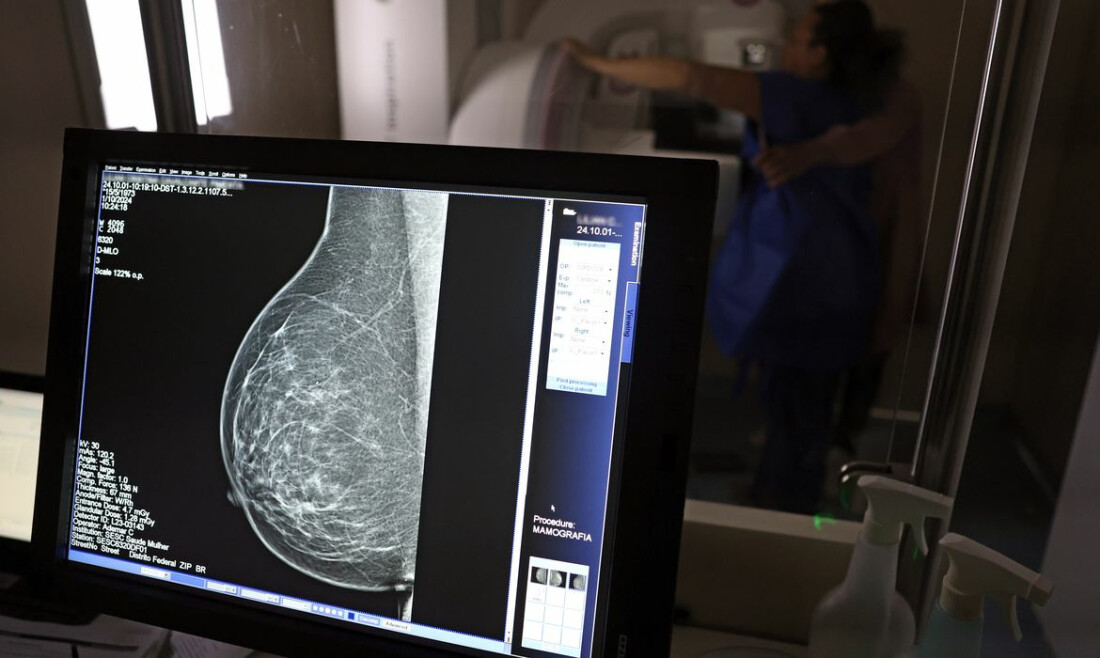

Em junho deste ano, 77.243 brasileiras aguardavam por uma mamografia no Sistema Único de Saúde (SUS). Santa Catarina é o estado com mais mulheres na fila de espera, cerca de 17 mil.  Em seguida, aparecem São Paulo (15 mil) e Rio de Janeiro (12,5 mil). Juntos, os três estados somam 56% do total de pacientes à espera do principal exame para detecção do câncer de mama. Os dados foram divulgados nesta quinta-feira (31) pelo Colégio Brasileiro de Radiologia e Diagnóstico por Imagem (CBR). Segundo a entidade, em alguns locais do país, o tempo de espera por uma mamografia na rede pública pode chegar a 80 dias. O exame, quando realizado em tempo hábil, permite a detecção precoce de alterações mamárias, aumentando as chances de tratamento bem-sucedido e reduzindo a necessidade de intervenções invasivas e onerosas. “Os números revelam parte da sobrecarga no SUS e devem ser levados em conta, especialmente pelos recém-eleitos nas eleições municipais, na formulação e manutenção de políticas de saúde pública”, avaliou o CBR. Subnotificação Em nota, a entidade alerta que a fila de espera por mamografias no SUS pode ser ainda mais longa do que o indicado oficialmente. “Isso porque o SISREG [Sistema de Regulação] do Ministério da Saúde, plataforma que deveria registrar em uma fila única as demandas por cirurgias eletivas no país, depende de dados fornecidos voluntariamente pelas secretarias de saúde estaduais e municipais.” “Um exemplo dessa discrepância pode ser observado no Distrito Federal, onde o sistema nacional informa uma fila de espera de 306 pacientes aguardando pelo exame. No entanto, dados divulgados pela imprensa local, baseados no Mapa Social do Ministério Público do Distrito Federal e Territórios (MPTDF), apontam que o número real de mulheres à espera de uma mamografia é dez vezes maior, alcançando 3,6 mil.”   Tabela mostra espera por mamografia nos estados do Brasi - SISREG/Ministério da Saúde Para o CBR, a disparidade entre regiões e o tempo médio de espera também figuram como preocupações no contexto da realização de mamografias no Brasil. A entidade aponta “necessidade urgente de intervenções eficazes e de políticas públicas capazes de reduzir as filas e garantir acesso equitativo ao diagnóstico”. Relatório recente publicado pelo Instituo Nacional de Câncer (INCA) sobre o controle do câncer de mama no Brasil aponta que longos períodos entre a solicitação do médico e a emissão do laudo podem dificultar a adesão da população ao rastreamento da doença. Em 2023, 48,8% das mamografias de rastreamento tiveram laudos liberados em até 30 dias após a solicitação do exame. Cerca de 36% dos laudos, entretanto, foram liberados com mais de 60 dias. Relacionadas Mulheres de baixa renda terão exames gratuitos de câncer de mama Outubro Rosa: mulheres têm exames gratuitos na rodoviária de Brasília